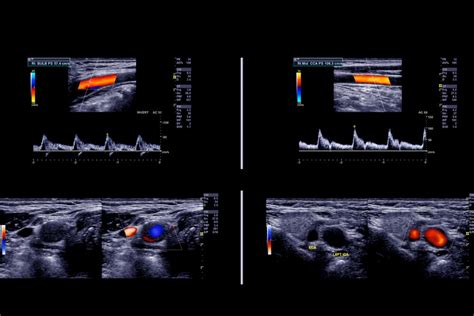

Die Diagnose einer Vasa praevia beginnt typischerweise mit einer gründlichen klinischen Untersuchung, einschließlich einer detaillierten Anamnese und körperlichen Untersuchung. Der Ultraschall ist das wichtigste Instrument zur Diagnose einer Vasa praevia. Bei Schwangeren mit Risikofaktoren wird ein Ultraschall im zweiten Schwangerschaftsdrittel (Trimenon) empfohlen. Dieser sollte mit der sogenannten Farbdoppler-Funktion sowohl transabdominal (durch die Bauchdecke) als auch transvaginal (durch die Vagina) durchgeführt werden. Im dritten Trimenon sollte die Diagnose überprüft werden, da sich Vasa praevia spontan zurückbilden können.

Bei Verdacht auf Vasa praevia aufgrund von Symptomen (schmerzlose vaginale Blutung, Membranruptur, fetale Bradykardie) und/oder Befunden während routinemäßiger pränataler Sonographie wird die Diagnose mittels transvaginaler Sonographie bestätigt. Dabei können die fetalen Gefäße in den Eihäuten gesehen werden, wie sie direkt über oder nahe des inneren Muttermundes vorbeiziehen. Ein Doppler-Farbfluss-Mapping wird verwendet. Es ist wichtig, Vasa praevia von einem Vorliegen der Nabelschnur (Prolaps der Nabelschnur) zu unterscheiden, bei dem die mit Wharton-Sulze umgebenen fetalen Blutgefäße die Zervix bedecken.